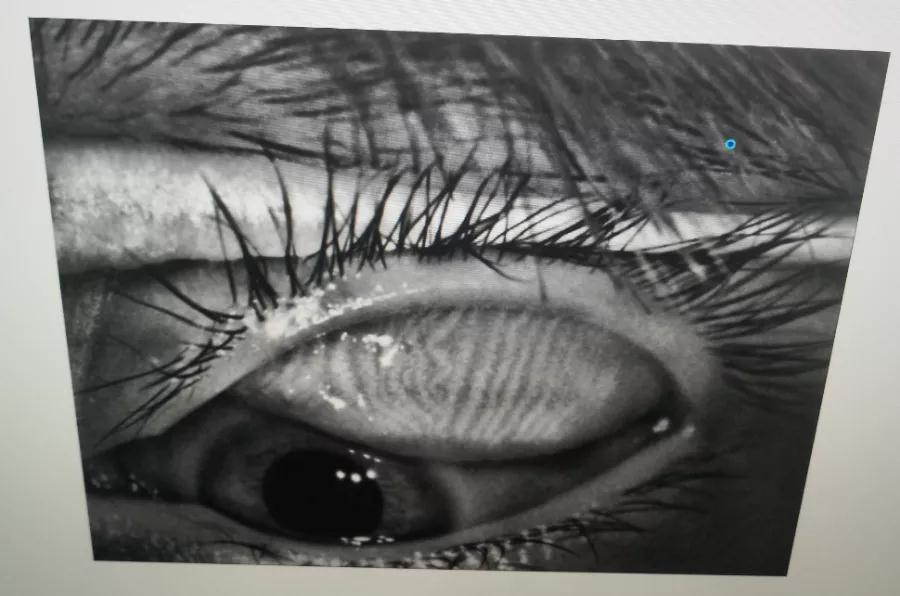

瞼板腺是排列在我們上下眼皮里面,分泌油脂的腺體,這些油脂是組成淚液的重要成分,可以讓淚水更長時間的停留在眼球表面。瞼板腺油脂減少,淚水蒸發(fā)就會加快,眼球暴露在外的時間變長,會加重眼睛干澀,時間一久,干眼也就隨之而來。

通過熱敷并按摩擠壓上下眼瞼,將瞼板腺內(nèi)不能自行排出的分泌物推出,疏通堵塞的瞼板腺開口。

熱敷可以促進眼周部位的血液循環(huán),瞼板腺按摩能有效改善瞼板腺功能,解決絕大多數(shù)干眼患者油脂分泌不足問題。

03、OPT強脈沖光

通過強脈沖光高溫消除蠕形螨蟲,同時脈沖光產(chǎn)生的熱量可以熔解軟化瞼酯,改善瞼板腺內(nèi)脂質(zhì)分泌物的流動性,疏通瞼板腺,提高淚膜的穩(wěn)定性,恢復(fù)正常眼表功能和眼部“鎖水”能力,從病因上治療干眼。